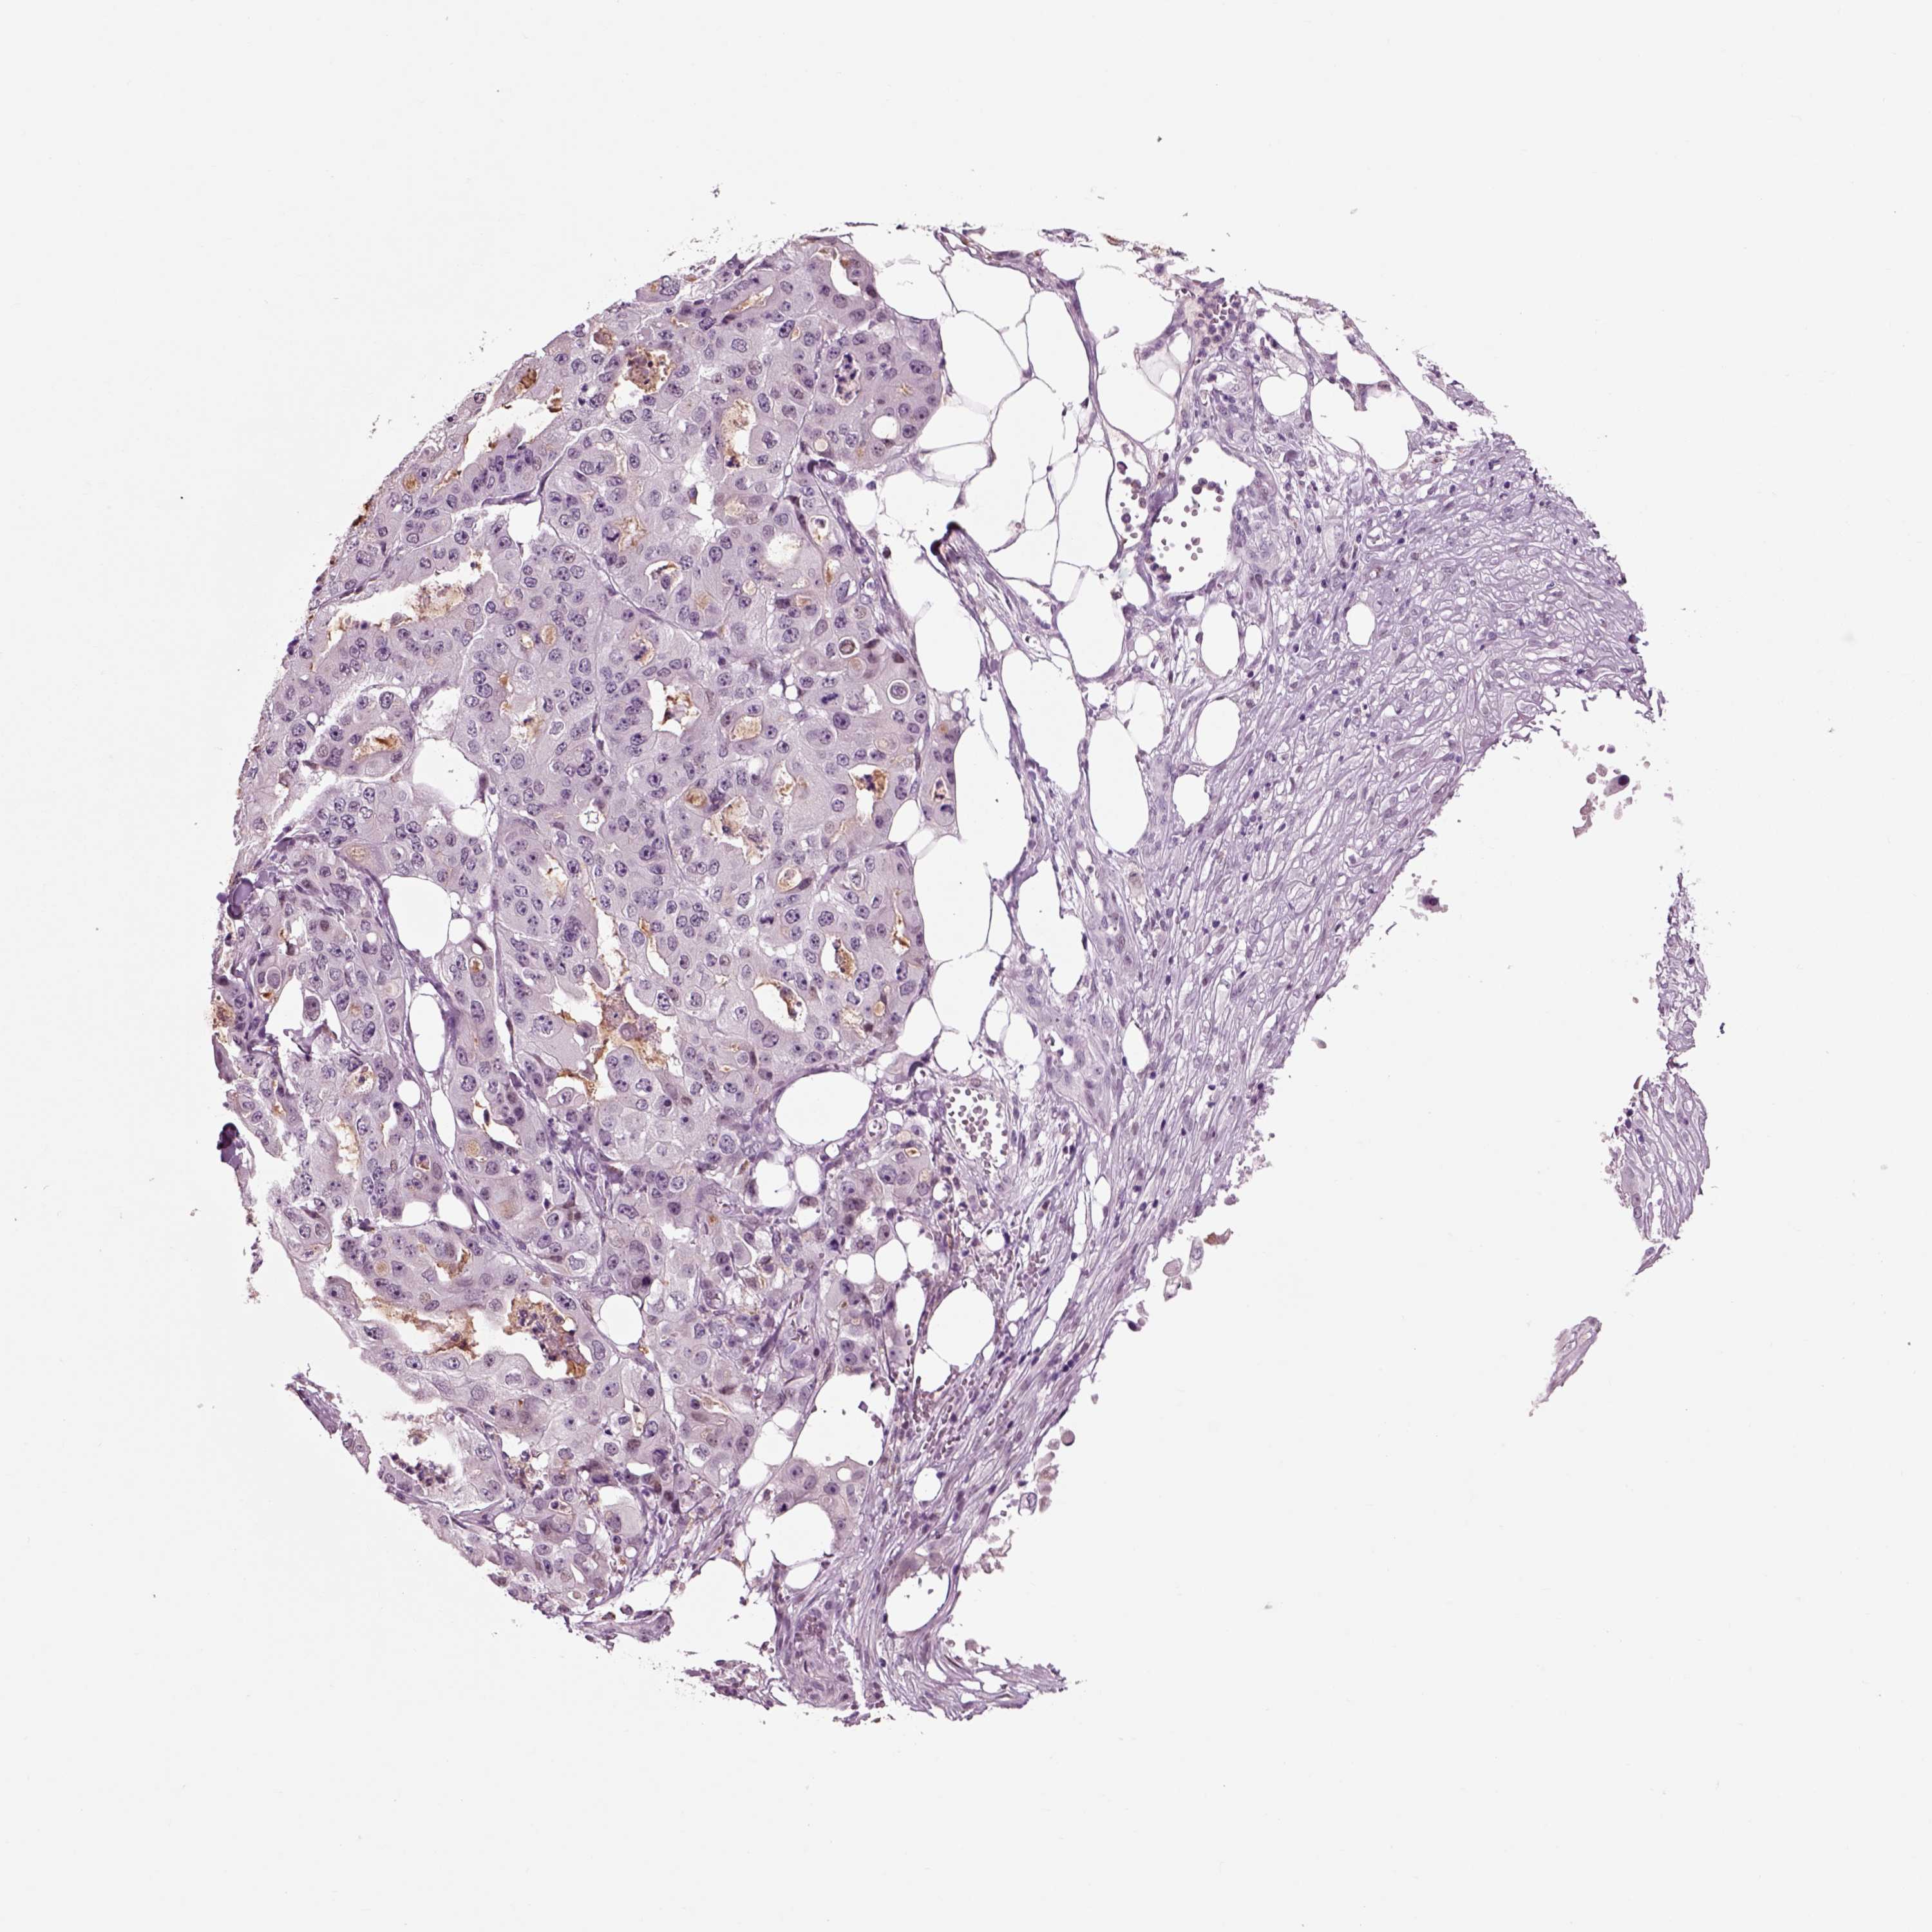

OVARIAN CANCER - Protein expressioni

A mouse-over function shows sample information and annotation data. Click on an image to view it in a full screen mode. Samples can be filtered based on level of antibody staining by selecting one or several of the following categories: high, medium, low and not detected. The assay and annotation is described here.

Note that samples used for immunohistochemistry by the Human Protein Atlas do not correspond to samples in the TCGA dataset.

Antibody stainingi

Antibody staining in the annotated cell types in the current human tissue is reported as not detected, low, medium, or high, based on conventional immunohistochemistry profiling in selected tissues. This score is based on the combination of the staining intensity and fraction of stained cells.

Each image is clickable and will lead to virtual microscopy that enables deeper exploration of all samples and also displays staining intensity scores, fraction scores and subcellular localization as well as patient and tissue information for each sample.

Antibody CAB009403

Cystadenocarcinoma, serous, NOS

Cystadenocarcinoma, mucinous, NOS

Carcinoma, endometroid